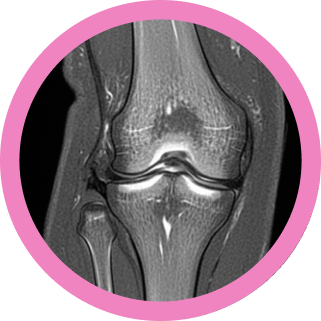

La Resonancia Magnética (MRI) se ha consolidado como una herramienta diagnóstica fundamental en el estudio de las patologías de la rodilla, superando en muchos aspectos a otras técnicas de imagen debido a su alta resolución de contraste para tejidos blandos y la ausencia de radiaciones ionizantes. La rodilla, como una de las articulaciones más complejas y sometidas a cargas constantes, es susceptible a una amplia variedad de lesiones, tanto traumáticas como degenerativas. Un diagnóstico preciso y oportuno es crucial para guiar el tratamiento adecuado y mejorar el pronóstico del paciente.